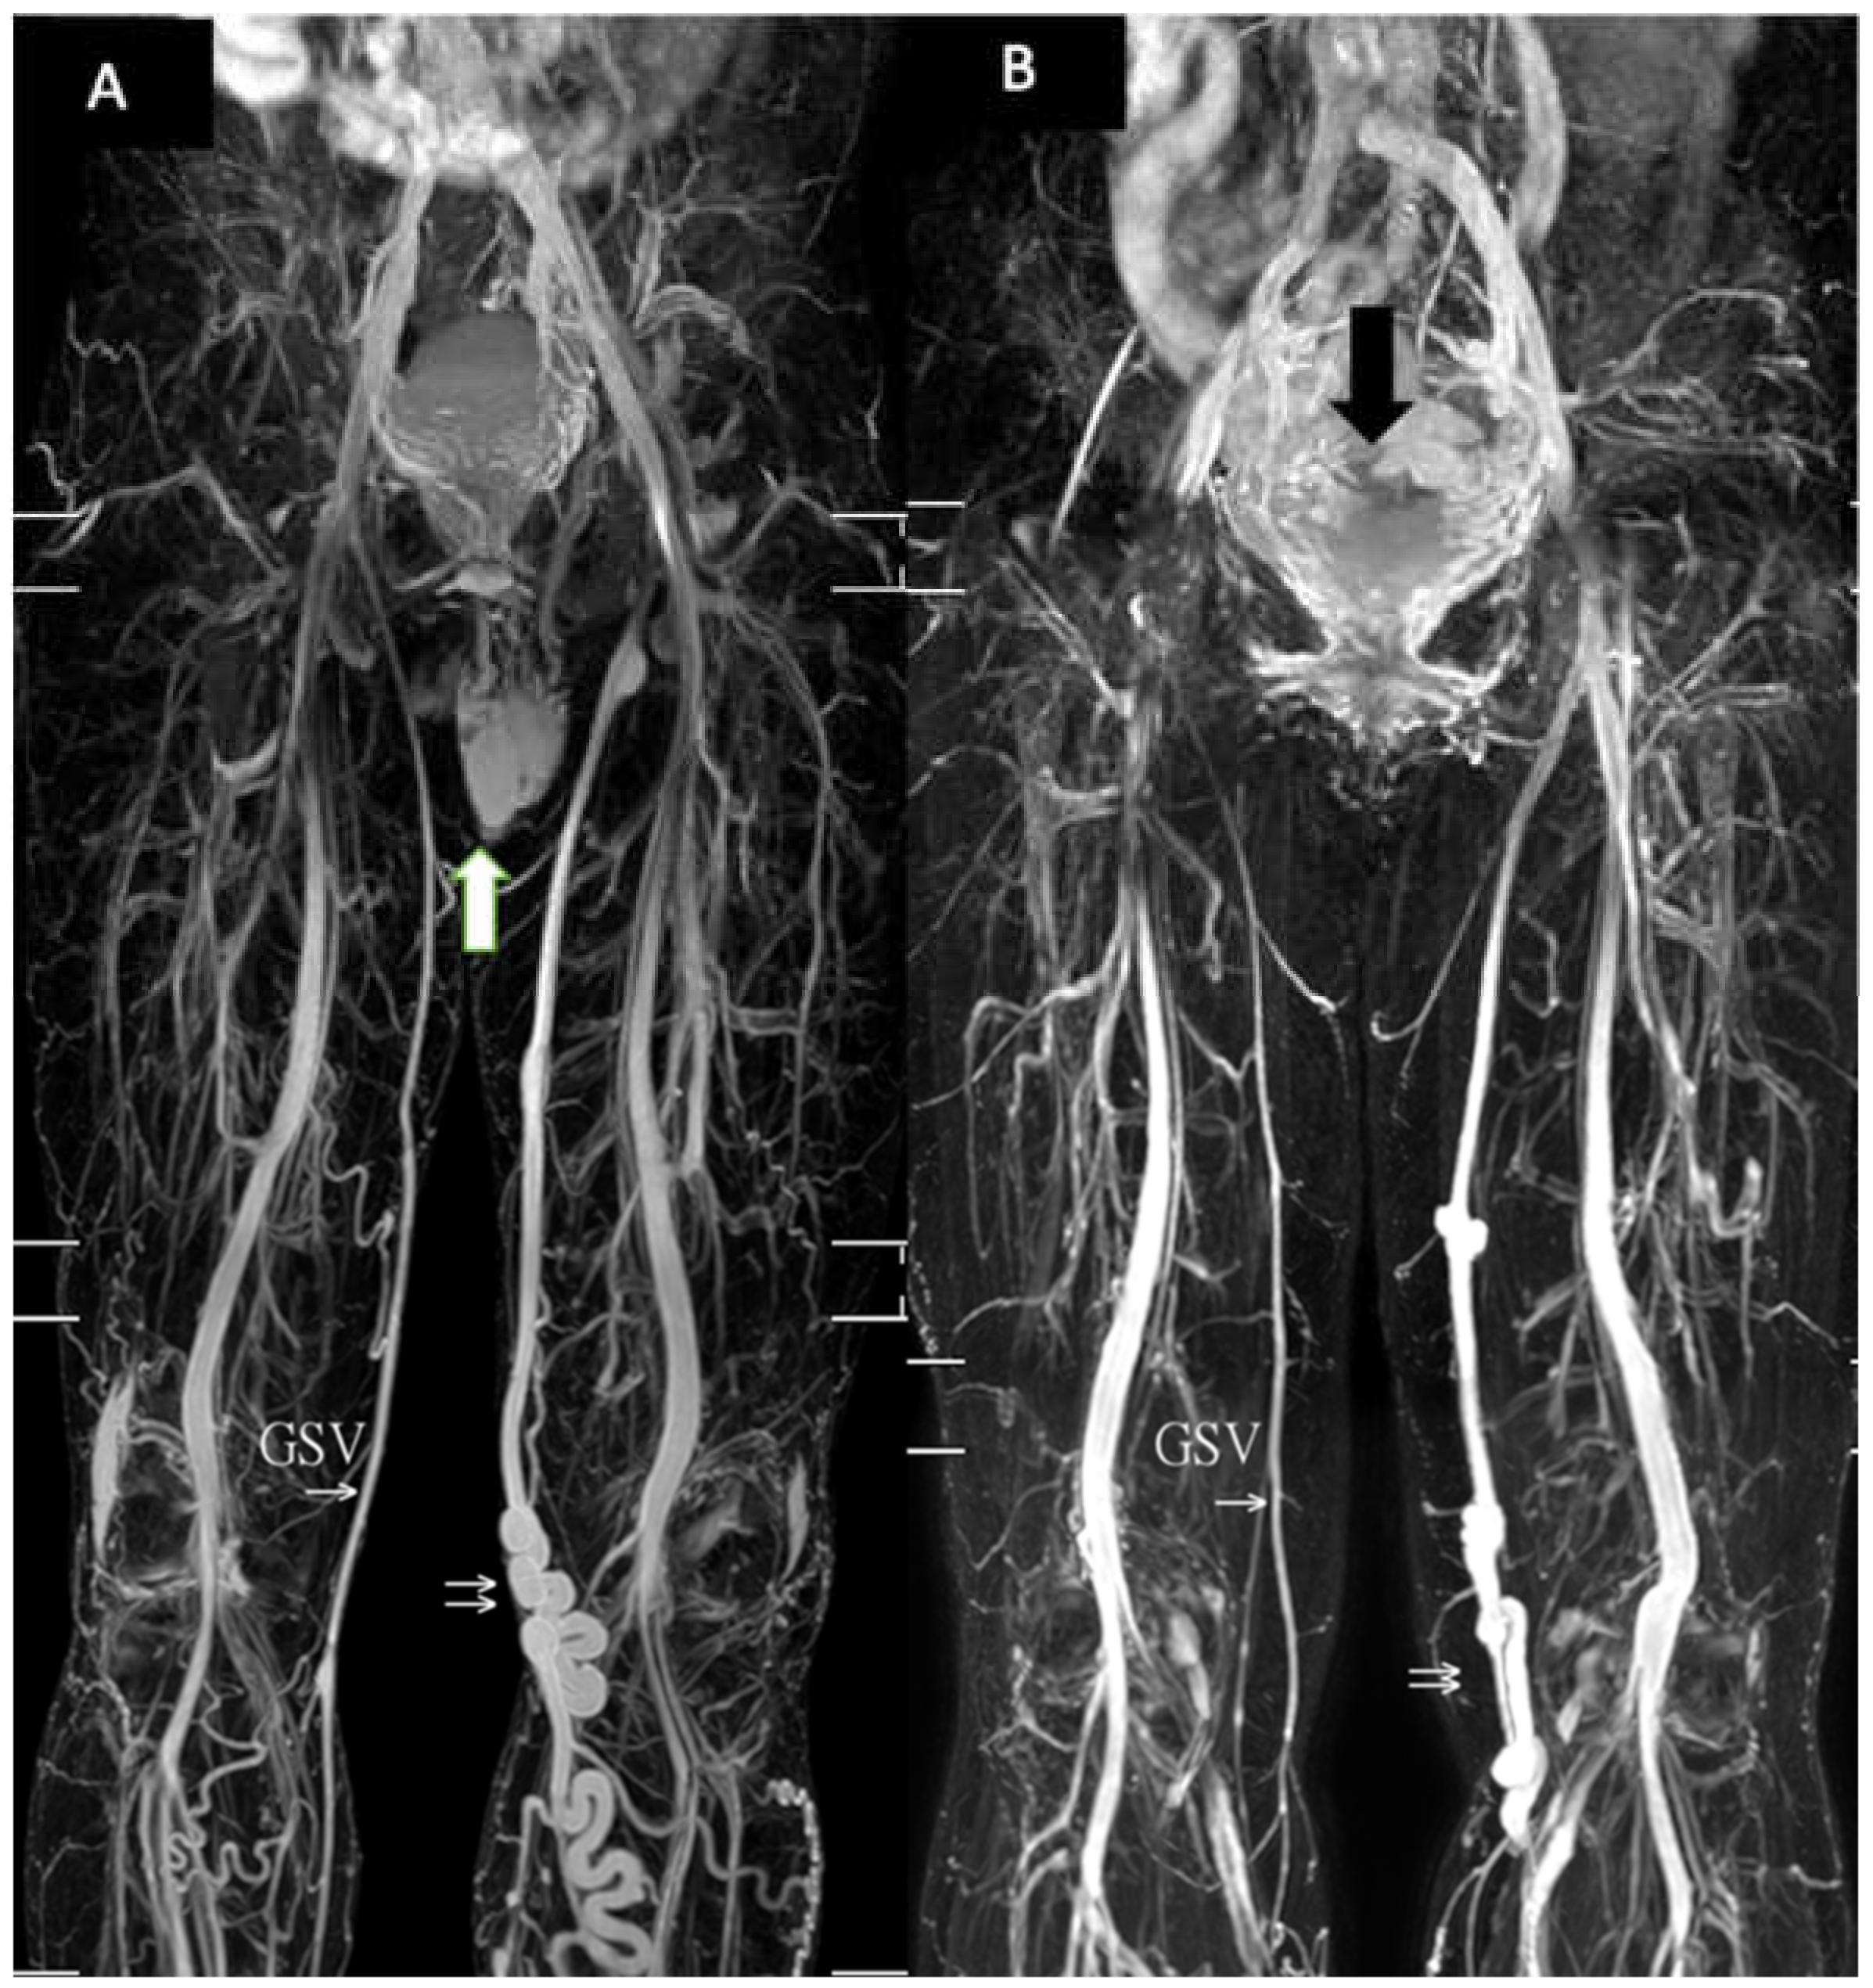

2. Methods

2.2. MRI Acquisition

3. Results

4. Discussion